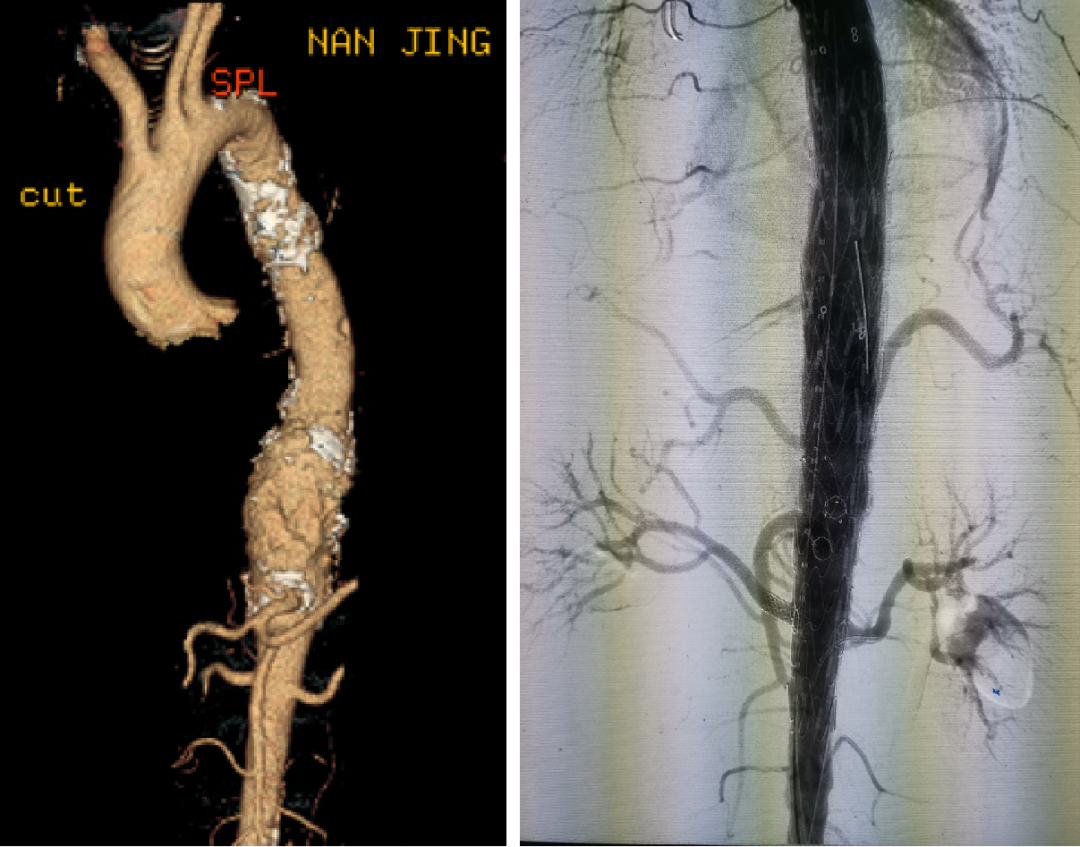

病例:复杂TAAD多次手术后,IIIc型内漏

术后2年随访:动脉瘤增大、左肾支架脱出

★ 大动脉瘤或偏心性动脉瘤术后

如果突然体位变化,有可能主体支架移位导致分支支架从窗口或内脏血管附着处脱出,引起内脏动脉急性阻塞和缺血。

预防措施:

建议至少置入两个分支支架,以固定主体和分支支架。